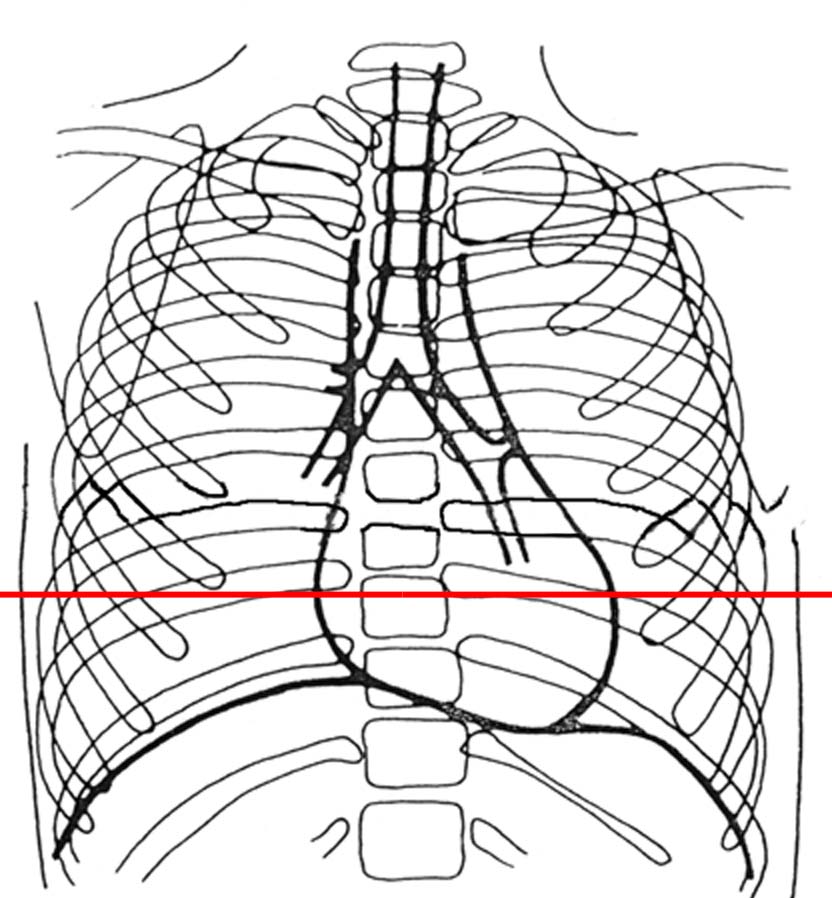

Syndrome alvéolaire

légendes

niveau de la coupe